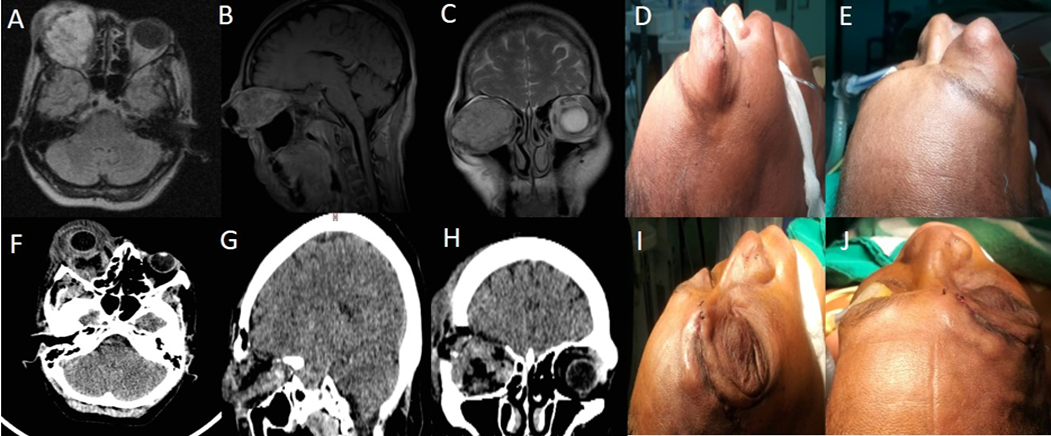

Se realizó como parte de la planificación quirúrgica estudio de resonancia magnética (RM) para conocer las características tumorales. Se efectuó una planificación quirúrgica para lesiones localizadas en sentido del reloj e inverso en la órbita izquierda: De 1-6, AEEE a la órbita; de 7-10, orbitotomía lateral con apoyo endoscópico; de 10-1, abordaje keyhole superciliar (Fig. 1 - Ver Fig. 1 en la resolución original).

Fase transoperatoria

En todos los pacientes se realizó tarsorrafia para cuidado del globo ocular. Se realizaron 3 abordajes quirúrgicos para acceso y resección de las lesiones.

Fase posoperatoria

En las primeras 24 horas se realizó estudio de tomografía axial computarizada (TAC) para identificar complicaciones. A los 30 días del posoperatorio se indicó una RM evolutiva para estimar el grado de resección tumoral.